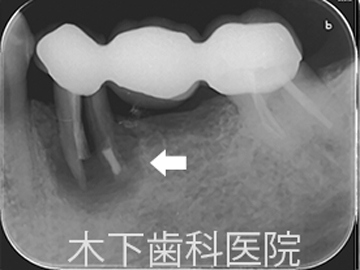

ブリッジは残っている歯に負担が増加することで、歯の破折のリスクが増加すると言われています。以下の写真はブリッジを支える片方の歯が折れてしまったレントゲン写真です。

長いブリッジを入れると残っている歯へさらに負担が増えるため、インプラントを入れることで残っている歯への負担を減らすことができ、ご自身の歯をより長く残す可能性が高まります。以下の写真は破折した歯を抜歯後、ブリッジを除去し、インプラントを2本入れた術後の写真です。